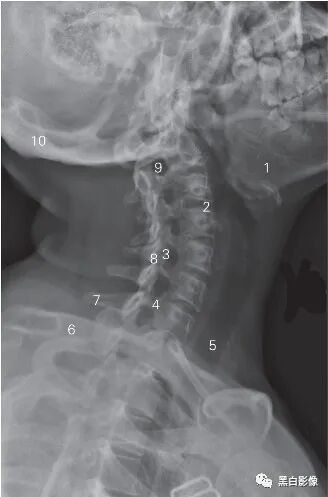

图6-2 颈椎侧位DR平片

1 枕骨 occipital bone 2 第2颈椎棘突 2nd cervical spinous process

3 关节突关节 zygapophyseal joint

4 下关节突 inferior articular process

5 上关节突 superior articular process

6 第4/5颈椎间隙 4th/5th cervical intervertebral space

7 横突 transverse process 8 第3颈椎 3rd cervical vertebra

9 颈2/3椎间孔 2nd/3rd cervical foramen intervertebrale

10 齿状突 odontoid 11 寰椎前弓 anterior tubercle of atlas